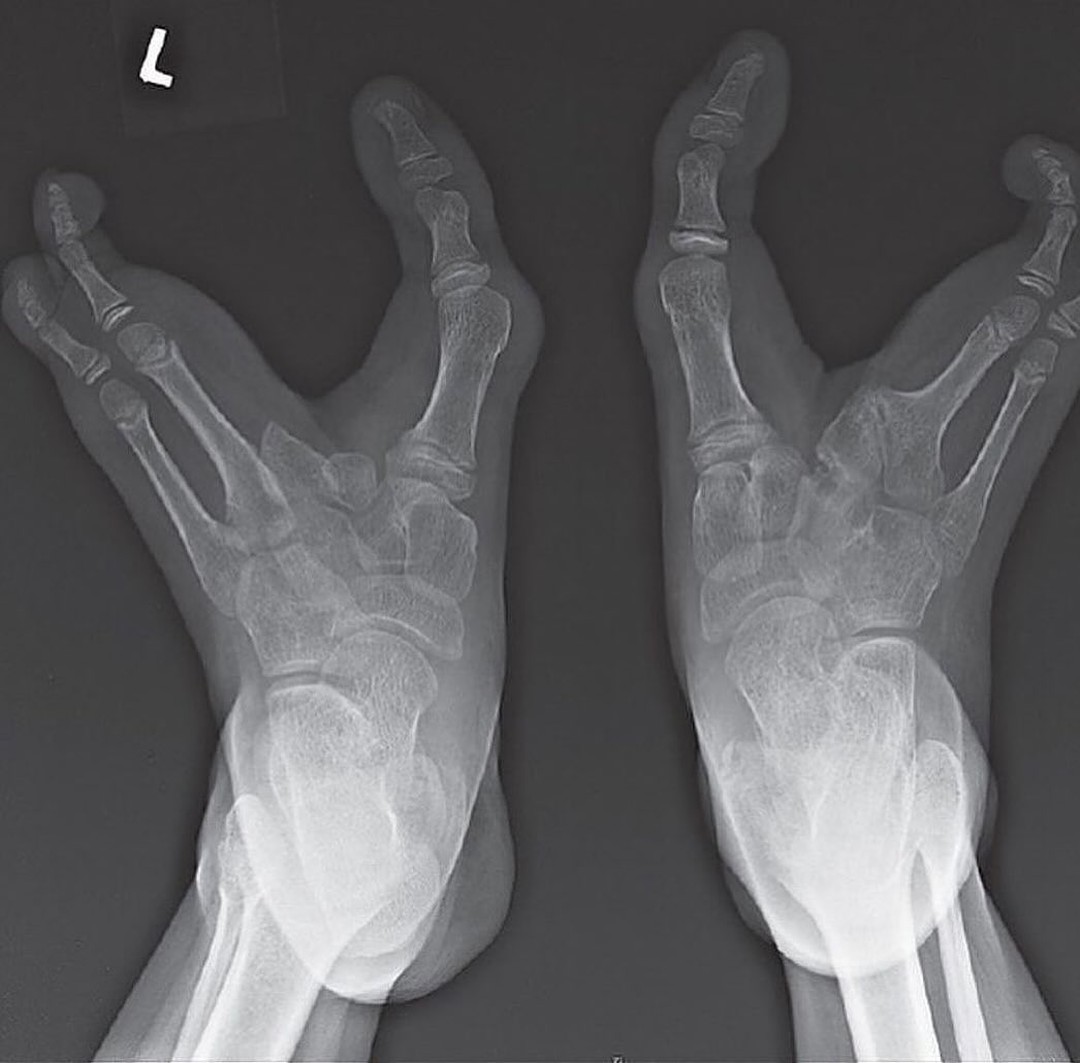

Científicamente, esta característica se conoce como ectrodactilia. Es una condición genética hereditaria que resulta en la ausencia de uno o más dedos centrales de las manos o los pies. En el caso de los Vadoma, es común que falten los tres dedos medios del pie, dejando únicamente los dos dedos exteriores, el primero (gordo) y el quinto (pequeño), a menudo curvados hacia adentro.

Esta condición no es exclusiva de África ni de esta tribu, pero su alta prevalencia en esta comunidad específica es un caso de estudio genético. La ectrodactilia de los Vadoma es un rasgo autosómico dominante, lo que significa que solo se necesita que uno de los padres porte el gen, producto de una mutación en el cromosoma 7, para que su descendencia tenga una alta probabilidad de heredarlo.